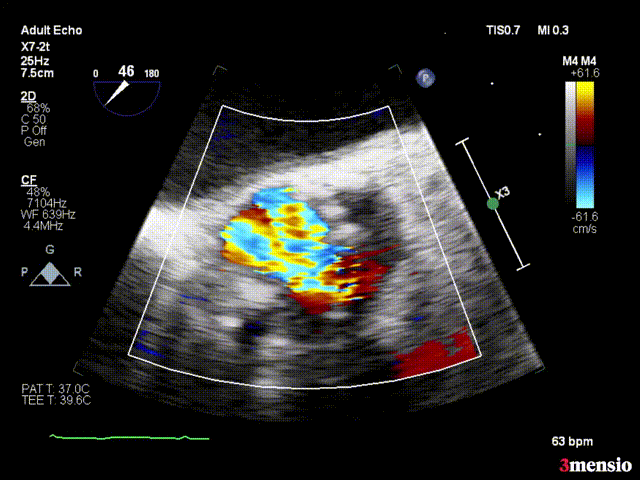

术前心脏超声结果显示,患者主动脉瓣开放明显受限,呈二叶式畸形(Type 0型),主动脉瓣前向血流Vmax 5.82m/s,平均跨瓣压差84mmHg。

超声心动图2